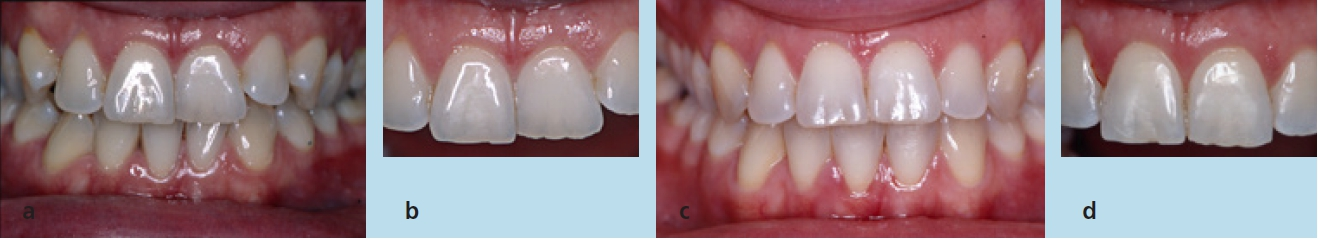

- Behandlung verschiedener Anomalien mit intermaxillärer Disharmonie, intramaxillärer Disharmonie oder Tiefbiss. Hierbei muss zwischen Schmelzreduktion und Extraktion abgewogen werden (Abb. 7a bis d)

- Ausgleich des Zahnvolumens: im Oberkiefer, nach Extraktion oder bei Fehlen eines Unterkieferinzisiven; im Unterkiefer aufgrund des Vorkippens der Inzisiven (Abb. 8a bis d)

Die erste Behandlungsalternative hätte zu einer Verschlechterung des fazialen Erscheinungsbildes geführt. Infolge der Extraktion und anschließend des kieferorthopädischen Lückenschlusses wäre es zu einer Abflachung des Mundprofils gekommen. Bei dieser Behandlungsvariante wäre aufgrund der größeren Zahnbewegungen mit einer wesentlich längeren Behandlungsdauer und den entsprechenden Risiken zu rechnen gewesen. Der Patientin wurden Vor- und Nachteile beider Alternativen erläutert. Sie entschied sich nach ausführlicher Aufklärung für die Non-Extraktionstherapie.

Um die Okklusion in der vertikalen Dimension zu kontrollieren und den knappen Überbiss nicht zu verlieren, wurden zwischen den oberen Eckzähnen einerseits und den unteren Eckzähnen sowie 1. Prämolaren andererseits up & down-elastics in Form eines Dreiecks eingehängt. In den später eingegliederten Stahlbogen wurde zudem eine entsprechende Extrusionsstufe für die Oberkieferfront eingearbeitet. Die Zahnbögen waren lückenlos ausgeformt und nivelliert. Im Seitenzahngebiet war die Okklusion auf Klasse I eingestellt, die Frontzahnstufe war in sagittaler und vertikaler Richtung physiologisch (Abb. 25a bis e). Es trat keine Profilveränderung ein (Abb. 26a bis c). Die Parameter der Fernröntgenaufnahme (Tab. 3) lassen die dentalen Veränderungen erkennen; aufgrund der Zahnhartsubstanzreduktion kam es zu einer vergleichsweise geringen labialen Kippung beider Fronten. Zur Retention wurde an den Ober- und Unterkiefereckzähnen ein Retainer fixiert. Zusätzlich wurden im Ober- und Unterkiefer Retentionsplatten eingesetzt.